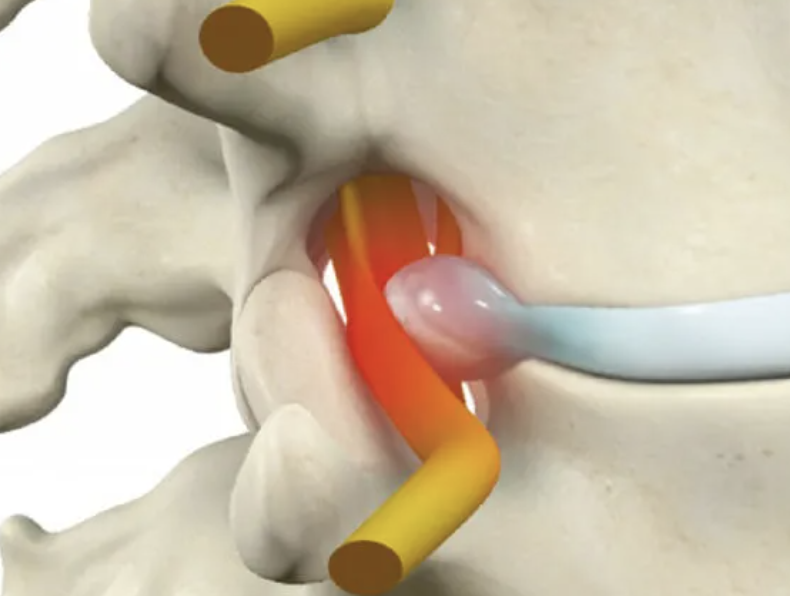

A hérnia de disco lombar é uma das causas mais comuns de dor nas costas e ciática. Ela ocorre quando o disco intervertebral uma estrutura de amortecimento entre as vértebras sofre uma lesão permitindo que o material gelatinoso interno núcleo pulposo se desloque para fora rompendo o anel fibroso externo. Esse deslocamento pressiona os nervos que passam por ali gerando dor e outros sintomas.

Os sintomas surgem da compressão e inflamação da raiz nervosa radiculopatia mais frequentemente em L4 a L5 ou L5 a S1.

Pode se apresentar com dor na região lombar baixa ou dor radicular com trajeto da dor dependendo do nervo acometido.

Em casos mais graves pode causar fraqueza muscular.